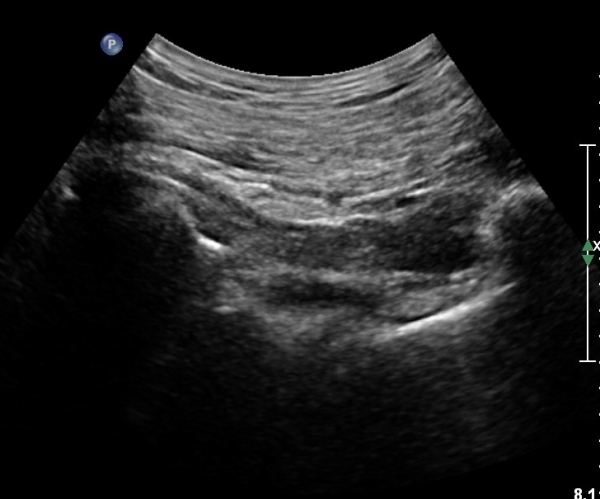

ŽÃÍÀÚ¸¦ ´Ù¸®ÂÊÀ¸·Î ¼öÆò À̵¿ÇÏ¸é ½ÉÃþ¿¡¼­ Àå°ñÀÌ »ç¶óÁö°í »õ·Î¿î ±ÙÀ°ÃþÀÌ º¸À̴µ¥ À̰ÍÀÌ ÀÌ»ó±ÙÀ̰í ÀÌ»ç±Ù ½ÉÃþ¿¡¼­ Á°ñ½Å°æ¸£ °üÂûÇÒ ¼ö ÀÖ´Ù(»çÁø 2, 3).